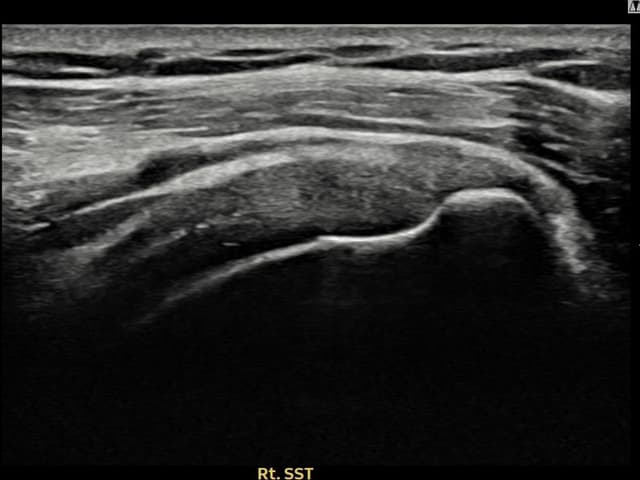

[촬영시기:23.09.01~23.11.03]

[어깨인대 축소봉합술] 우측 어깨 통증이 수개월간 지속되어 내원하셨습니다.